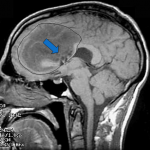

El fármaco experimental (llamado AMG 595) está destinado a dirigirse a un receptor específico de células mutadas (EGFRvIII) que existe en la superficie de las células tumorales hasta en un 30 por ciento de los pacientes con gliomas malignos. Estudios preliminares en animales han demostrado que las moléculas de ADC puede encontrar con eficacia estas células de cáncer específicas, a continuación, entrar en ellos y liberar un agente citotóxico muy activo con el fin de matar las células tumorales, mientras que minimiza el daño a los tejidos circundantes normales.

Los pacientes que han fracasado las terapias de primera y segunda línea para el glioma maligno pueden calificar para participar en este ensayo. Los posibles candidatos serán examinados para detectar la mutación EGFRvIII utilizando muestras tumorales obtenidas durante la cirugía original antes de la inscripción.